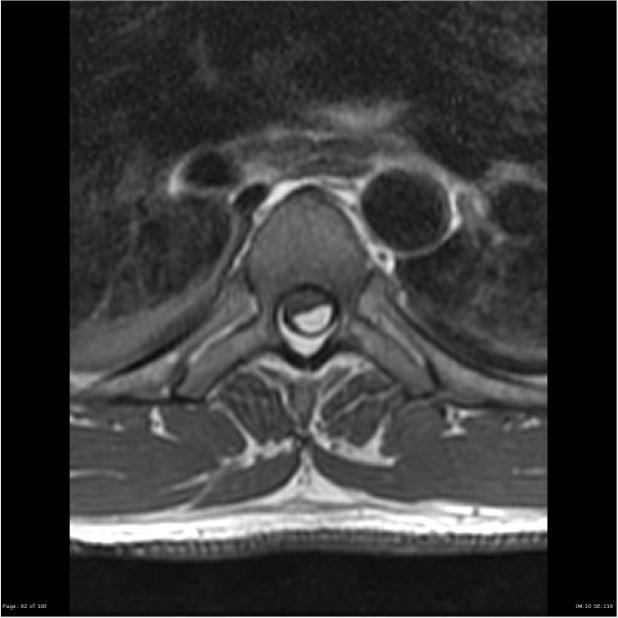

PRIMARY NEURULATION DEFECT

OPEN SPINAL DEFECT OSD MYELOCELE, MYELOSCHISIS

The placode remains “flat” and meninges are deep to the bony defect

OPEN DEFECT, CHIARI II MYELOMENINGOCELE

MMC

Placodr extends beyond the spinal defect, into a dilated cyst